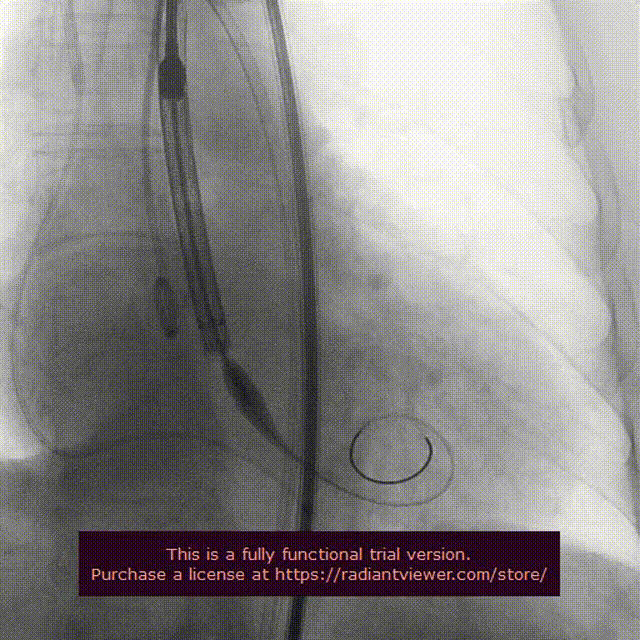

瓣膜定位释放

瓣膜释放过程

瓣膜完整形态

在影像、超声的共同指引下,术者团队通过调整输送系统至最佳位置实现精准释放,患者跨瓣压差即刻显著下降至0mmhg。再行主动脉造影提示瓣膜置入位置良好、形态完整,超声提示未见明显瓣周漏。术中及术后未出现相关并发症,圆满取得此次手术成功。